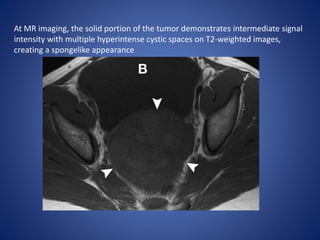

At MR imaging, the solid portion of the tumor demonstrates intermediate signal

intensity with multiple hyperintense cystic spaces on T2-weighted images,

creating a spongelike appearance

• 63.

At MR imaging,the solid portion of the tumor demonstrates intermediate signal intensity with multiple hyperintense cystic spaces on T2-weighted images, creating a spongelike appearance